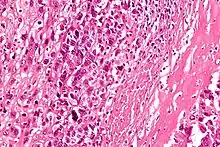

| Intermediate-magnification micrograph of an osteosarcoma (center and right of image) adjacent to non-malignant bone (left-bottom of image): The top-right of the image has poorly differentiated tumor. Osteoid with a high density of malignant cells is seen between the non-malignant bone and poorly differentiated tumor (H&E stain). | |

Microscopically: The characteristic feature of osteosarcoma is presence of osteoid (bone formation) within the tumor. Tumor cells are very pleomorphic (anaplastic), some are giant, numerous atypical mitoses. These cells produce osteoid describing irregular trabeculae (amorphous, eosinophilic/pink) with or without central calcification (hematoxylinophilic/blue, granular)—tumor bone. Tumor cells are included in the osteoid matrix. Depending on the features of the tumor cells present (whether they resemble bone cells, cartilage cells, or fibroblast cells), the tumor can be subclassified. Osteosarcomas may exhibit multinucleated osteoclast-like giant cells.[20]